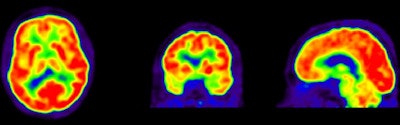

In recent years, both FDG and PiB have become more prominent biomarkers in the diagnosis of several forms of dementia, Ossenkoppele noted. PiB is designed to detect deposits of amyloid plaque in the brain, which have been associated with the onset of Alzheimer's disease. FDG measures metabolic activity of the brain at rest and has been used to distinguish between several forms of dementia.

Researchers then proceeded to the PET scans. First, patients were imaged with PiB for 90 minutes to obtain parametric images of the biomarker binding to potential clusters of amyloid. FDG-PET scans were then conducted 45 to 60 minutes after injection and lasted for 15 minutes. Standardized uptake value (SUV) ratios were calculated throughout the brain.

The resulting PET images were visually assessed by a nuclear medicine physician and reported to the neurologists to determine how the additional information changed their initial clinical diagnoses and their confidence in those interpretations.

In the Alzheimer's group, PET with PiB or FDG confirmed a total of 44 (67%) of the 66 cases prior to PET imaging. The second-greatest change was among patients with frontotemporal dementia. PET with PiB or FDG confirmed 11 (61%) of the 18 cases prior to PET.

PiB-PET scans were positive in 40 (61%) of 66 patients with clinical Alzheimer's and in five (28%) of 18 patients with clinical frontotemporal dementia. FDG SUV patterns matched the clinical diagnosis in 58% of patients with Alzheimer's and 33% of patients with clinical frontotemporal dementia, the authors noted.